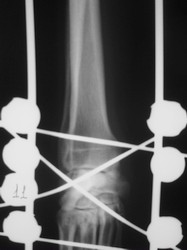

PRÁCTICAS CURSO DE FIJACIÓN EXTERNA PERFECCIONAMIENTO.

Artrodesis carpo.